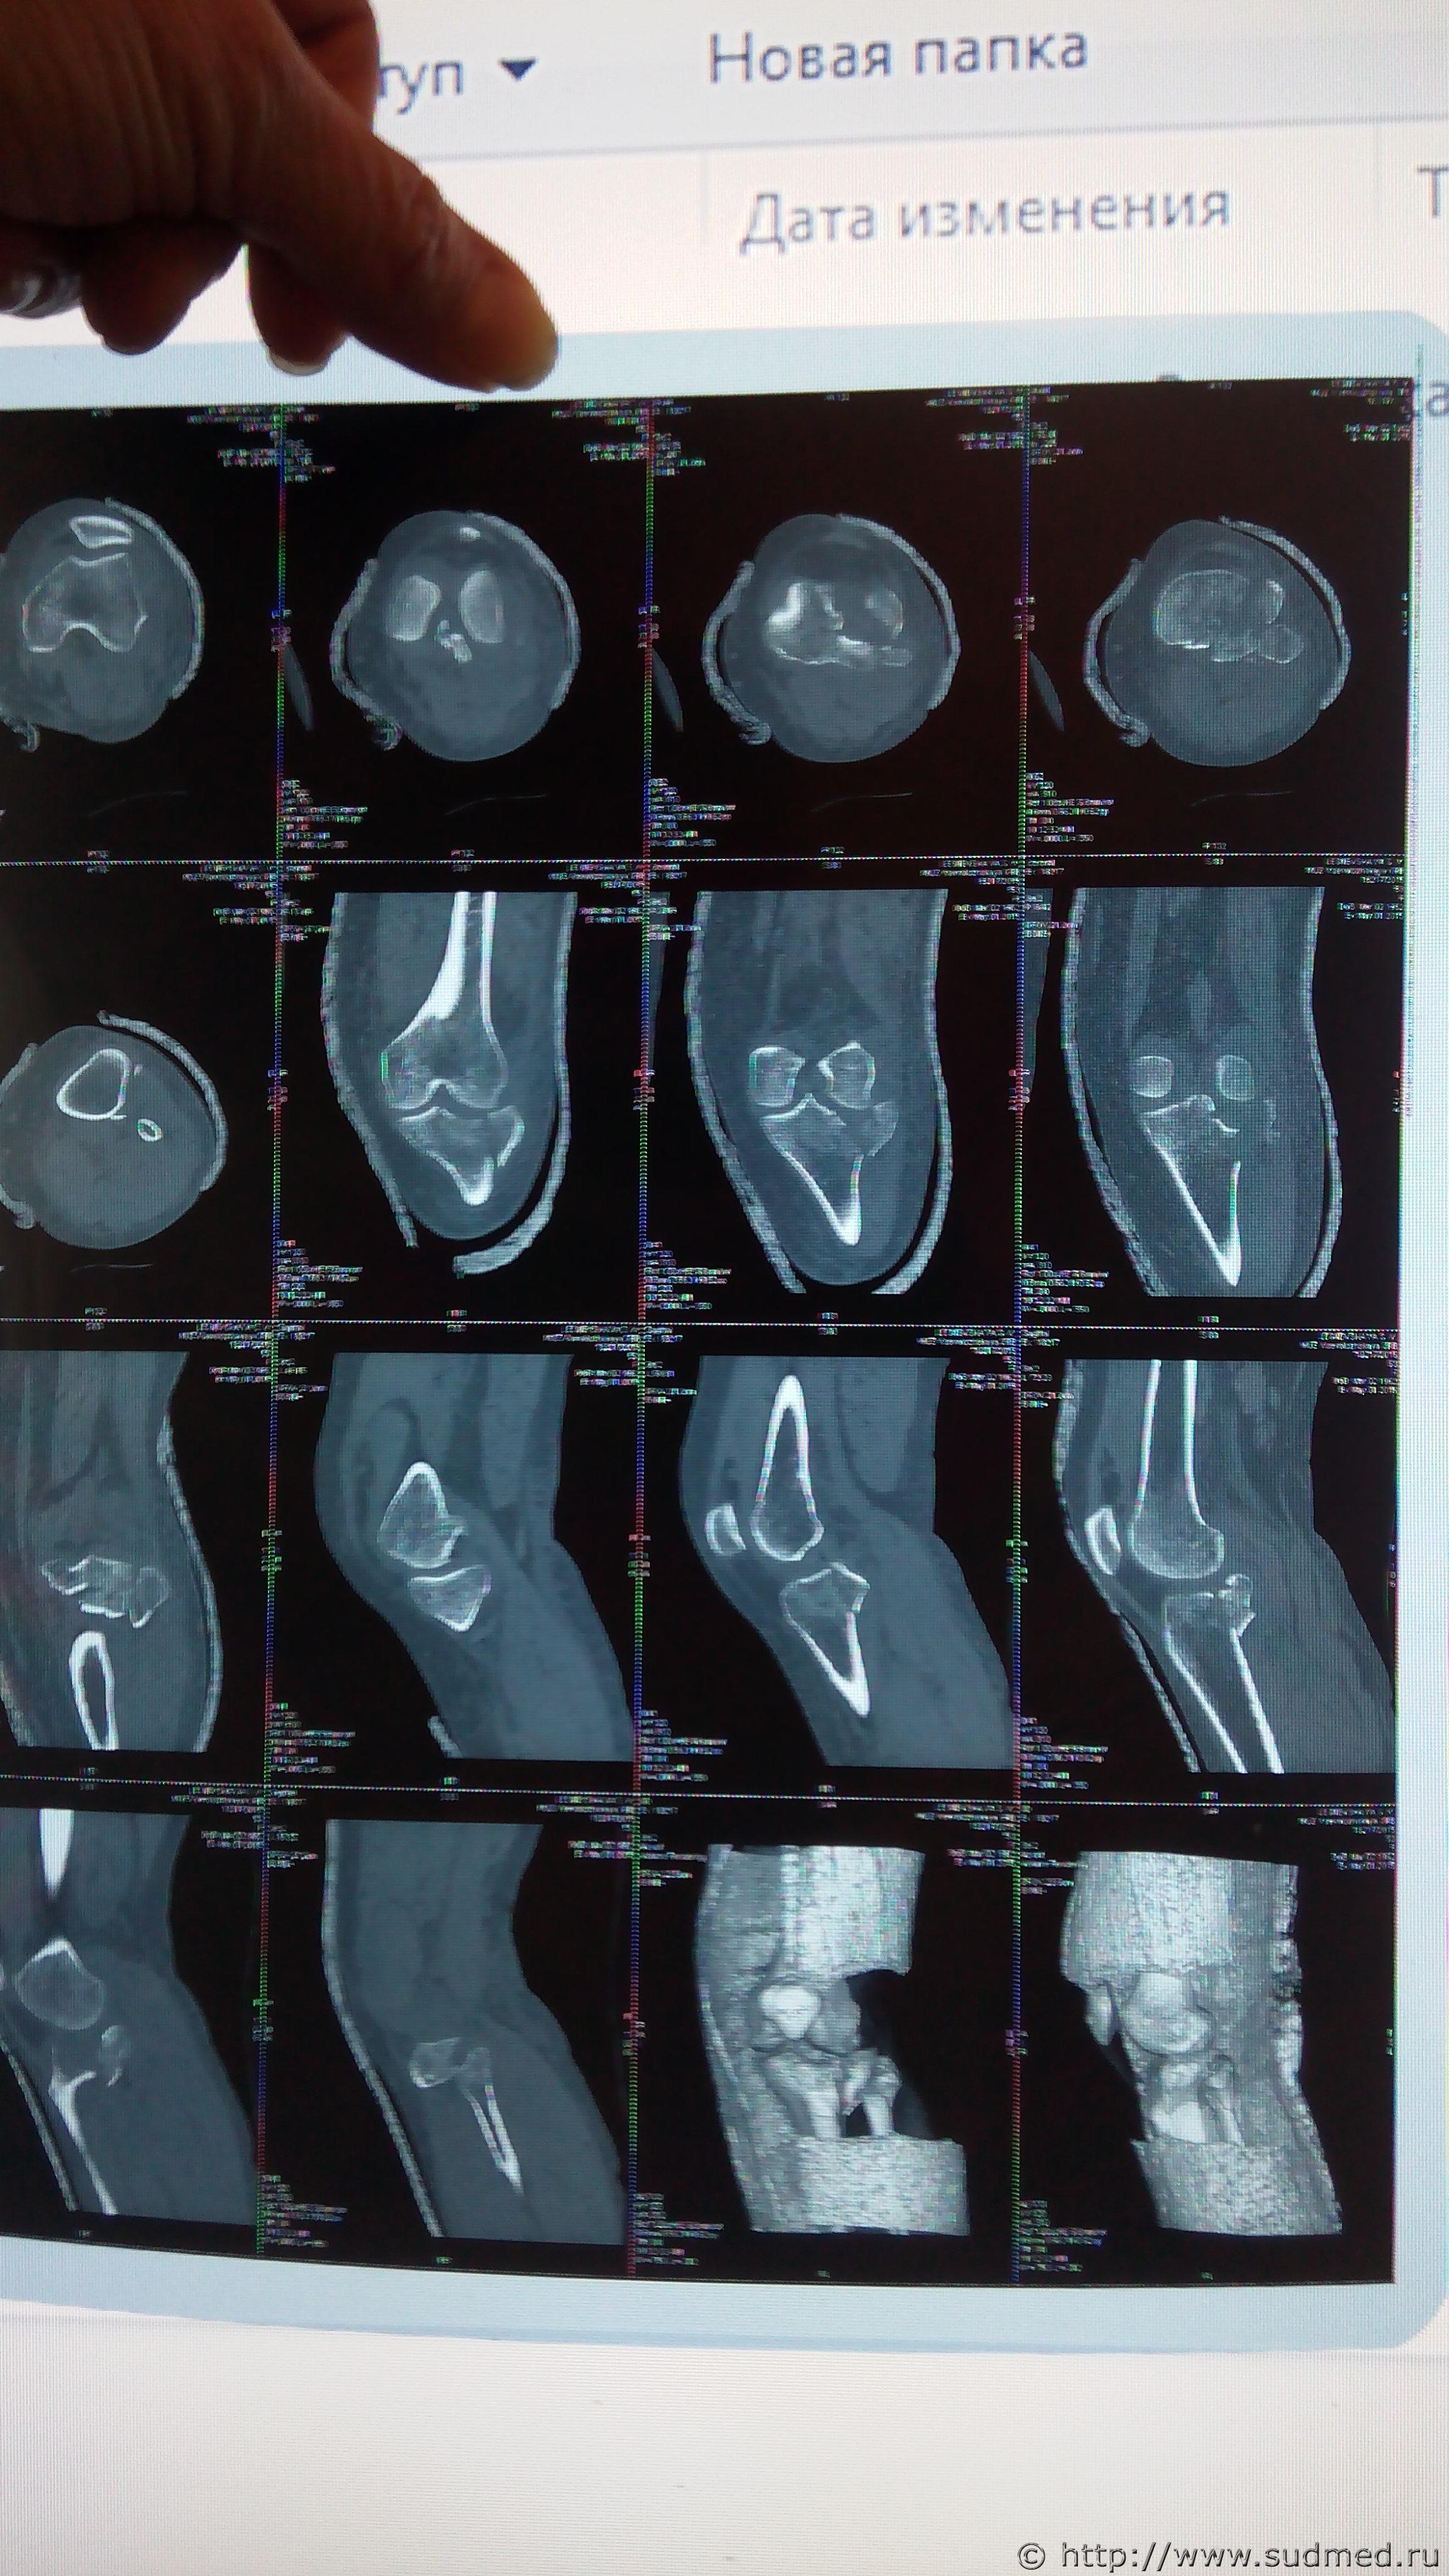

Спасибо за ответы , снимки послали должны появиться

Эскизы прикрепленных изображений

Судебная медицина - Прикрепленное изображение Судебная медицина - Прикрепленное изображение Судебная медицина - Прикрепленное изображение

На пленке представлено мало сканов КТ. + смотреть пленку или сканы в цифровом виде - намного лучше, чем их фотокопии, переданные через интернет.

Оптимально: 1.попросить рентгенолога скинуть Вам на флешку или на CD-диск ВСЕ сканы КТ коленного сустава (во всяком случае - ВСЕ выполненные в костном режиме - фактически их выполнено в несколько раз больше, чем напечатано на пленке). 2. попросить этого же и/или другого опытного рентгенолога внимательно посмотреть их все с единственной целью - установить, есть ли перелом диафиза большеберцовой кости (распространяется ли на него линия перелома) или же диафиз большеберцовой кости абсолютно цел. 3.Если признаков перелома диафиза нет - значит, тяжкого вреда здоровью именно за перелом кости нет (про нарушение функции сустава и невропатию - совсем отдельное дело, не о нем сейчас речь). Если же имеются рентгенологические признаки даже минимального распространения линии перелома на диафиз большеберцовой кости, тогда получаете официальное (письменное) заключение рентгенолога (рентгенологов) об этом, ходатайствуйте о доп.экспертизе с обязательным предоставлением на экспертизу всех рентгенограмм, КТ, заключений рентгенологов (о переломе диафиза большеберцовой кости).